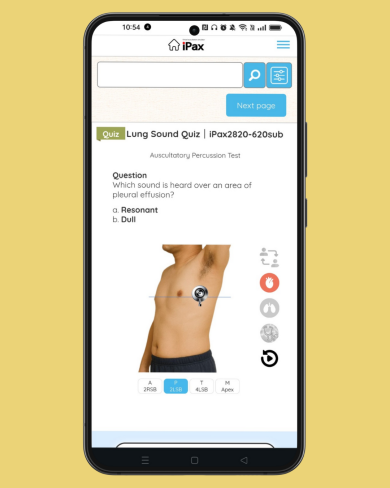

June 18 – Question on Crackles Today’s question focuses on crackles. The question includes a description of the characteristics of the crackling sound. Please listen to the two MP3 audio files and choose the one that matches the description. (June 18, 2025)